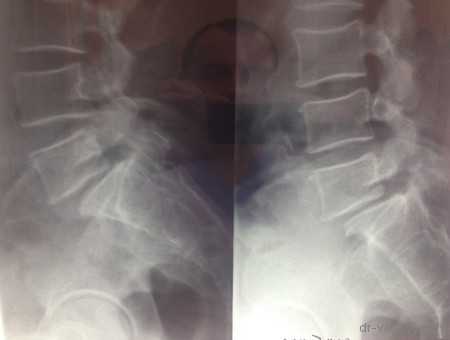

Рентген до операции

Фото транспедикулярной фиксации позвоночника